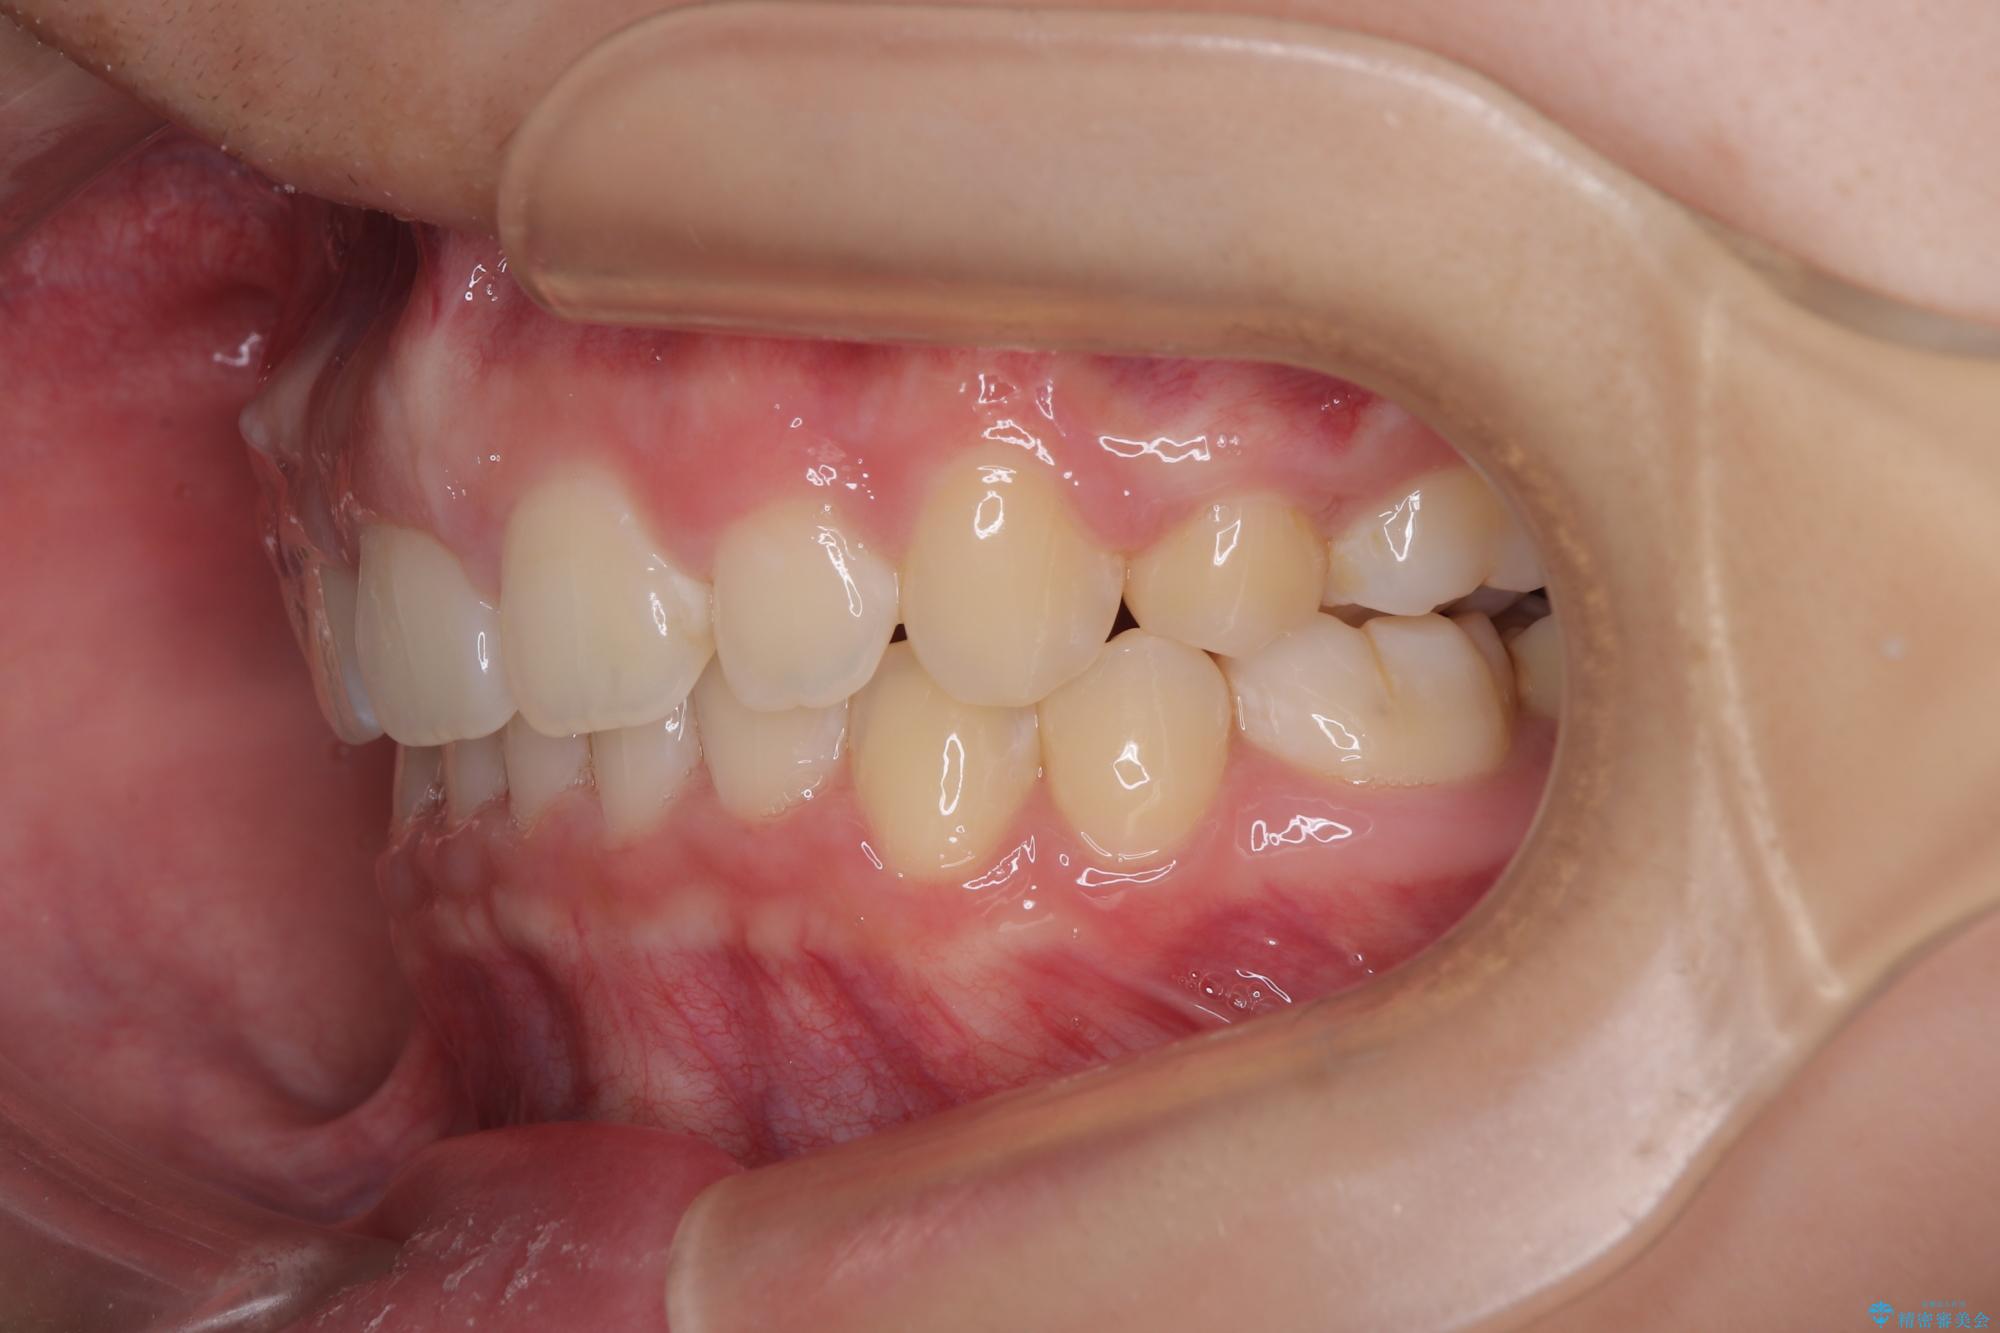

- 上顎前歯が飛び出していて唇がうまく閉じられないとのことで来院された患者様です。

くちばしのように前歯が突出していたため、口元を積極的に引っ込めるために、上下左右の小臼歯4本を抜歯することとしました。

また、上顎歯列が下顎に対して前方位に位置していたため、補助装置を用いて上顎歯列を後方に移動させ、より積極的に口元を下げるようにしました。

上下正中位置を改善するため、左下はイレギュラーに第二小臼歯を抜歯しました。そのため治療期間の長期化が予想されましたが、2年半ほどで期待通りの歯列に仕上げることができました。